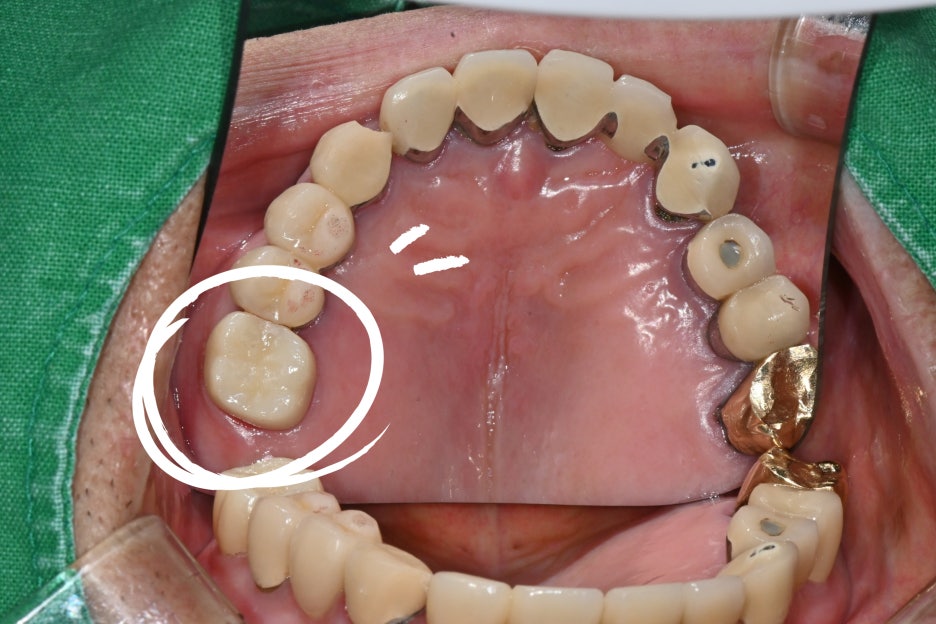

환자분의 어금니는 보철물 아래로

충치가 진행되어 치아 뿌리 근처까지

손상된 상태였기 때문에

신경치료가 필수적이었습니다.

첫방문 - 진단과 응급조치

오른쪽 위 어금니가 씹을 때마다 시큰거리고

차가운 물을 마시면 심하게 시려요

환자분은 치주염과 치석이 많이 쌓여 있어

우선 파노라마 촬영과 치석 제거를 진행했습니다.

검사 결과는 다음과 같았습니다.

1.오래된 보철물 아래로 충치 진행

2.만성 치주염 동반

3.잇몸 부종 및 출혈

4.신경 염증 가능성 높음

정밀 파악을 위해 추가로 치근단 엑스레이를 촬영했고, 실제로 치아 뿌리 끝까지 염증이 퍼져 있는 것이 확인되었습니다. 이 단계에서 신경치료 계획을 확정했습니다.